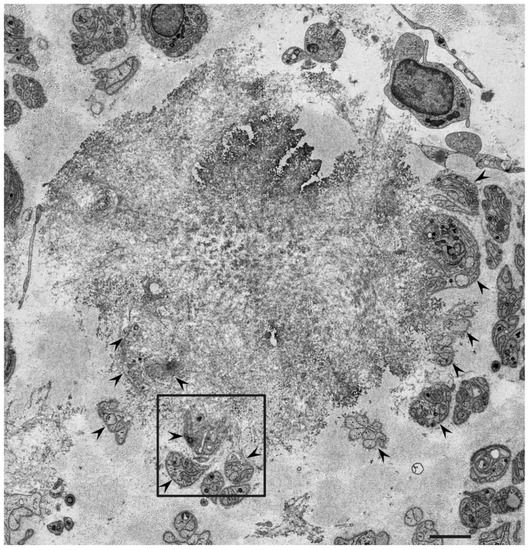

3.1. Atrophy and Degeneration Induced by Amyloid Fibrils

- Koike, H.; Ikeda, S.; Takahashi, M.; Kawagashira, Y.; Iijima, M.; Misumi, Y.; Ando, Y.; Ikeda, S.-I.; Katsuno, M.; Sobue, G. Schwann cell and endothelial cell damage in transthyretin familial amyloid polyneuropathy. Neurology 2016, 87, 2220–2229. [Google Scholar] [CrossRef]

- Koike, H.; Nishi, R.; Ikeda, S.; Kawagashira, Y.; Iijima, M.; Sakurai, T.; Shimohata, T.; Katsuno, M.; Sobue, G. The morphology of am-yloid fibrils and their impact on tissue damage in hereditary transthyretin amyloidosis: An ultrastructural study. J. Neurol. Sci. 2018, 394, 99–106. [Google Scholar] [CrossRef]